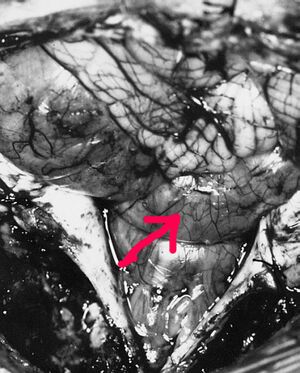

Операционная рана. Между мозжечком (сверху) и продолговатым мозгом (снизу) располагается выпирающая из IV желудочка в субарахноидальное пространство ткань эпендимомы

Наиболее частым местом расположения эпендимом является IV желудочек головного мозга. Клиническая картина опухолей IV желудочка складывается из явлений внутричерепной гипертензии, которая возникает вследствие нарушения оттока ликвора, а также очаговых симптомов. Последние возникают вследствие давления новообразования на расположенные в стенках IV желудочка структуры, то есть на ядра черепных нервов, на задний продольный пучок и на проводящие пути мозжечка[21].